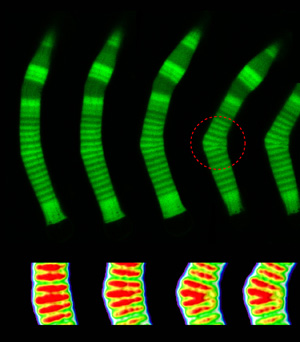

To address this question, Ahmadi and her team examined tadpole photoreceptors under the microscope while subjecting them to fluid forces. They found that high-density bands packed with a high concentration of rhodopsin were very rigid, which made them more susceptible to breakage than low-density bands consisting of less rhodopsin. Their model confirmed their experimental results and revealed factors that determine the critical force needed to break the outer segment.

![]() |

| SUNY Cortland Assistant Professor of Physics Aphrodite Ahmadi's study encompassed the basics of eye rod flexibility. This genetically fragile rod is shown bending as it begins to fail. The above left image, which details the rods bending, appeared in the Biophysical Journal and is reproduced here with the journal's permission. |

When looked at under a microscope, the rod photoreceptor cells in a tadpole eye appeared to gradually bend into a crook like a boomerang and break. Eventually, the rods no longer will transfer visual information to the brain.